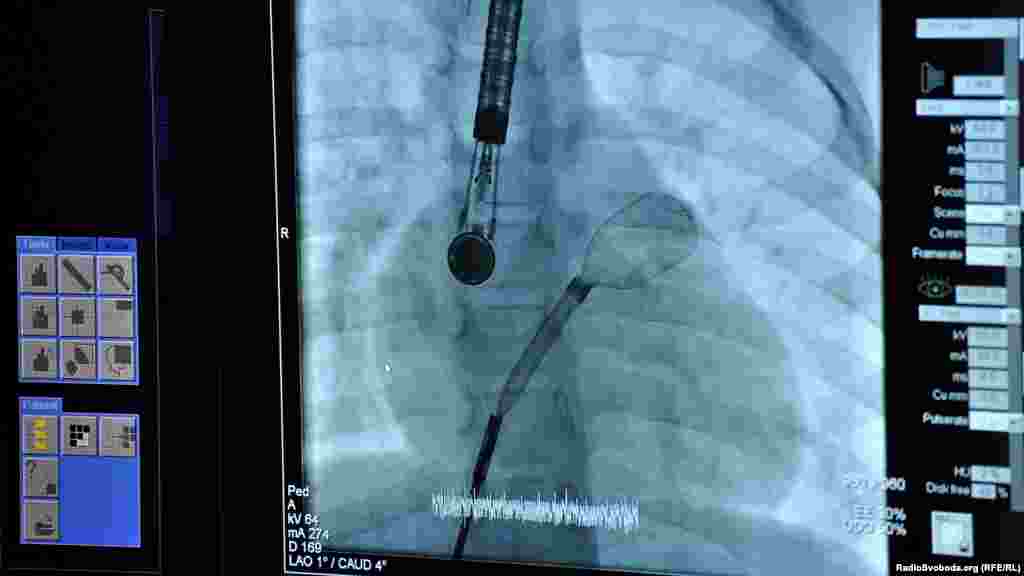

Введення оклюдера і датчиків до аорти. Зображення передається з датчика на екран

Введення оклюдера і сенсорів до аорти. Зображення передається з сенсора на екран